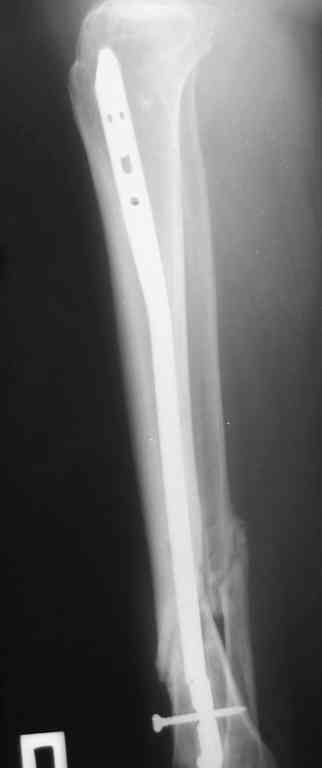

Re: Ложный сустав голени перелом штифта

Прилагаются.

Да , обсуждалась и оптимальным штифтом был выбран " Мастер" Остеомед 10 мм и винты 5 мм, но увы все наши благие намерения разбились о нашу действительность и материальные возможности больной, обращение ее в страховую компанию и т.д., вообщем выкручивались из внутренних резервов, а они были такими 9 мм штифт Остеомед, под 4 мм винты. Ограничили нагрузку. Ошиблись еще и с оценкой сращения, дали полную нагрузку+ больная поправилась на 18 кг, и вот теперь имеем , что имеем.

Действитльность и возвожности остались прежнее, во внутренних резервах есть 11 мм стержень универсальный ( реконструктивный) "Деост-CHM" много спиц и аппарат + ось конечности и отломок штифта и надежда на Ваши советы.